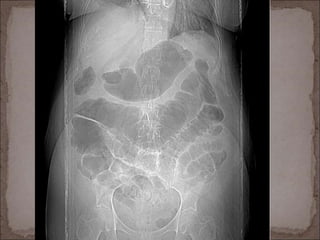

 Rx simple abdomen: +/- signos de obstrucción int. Delg.,

neumatosis, edema de pared, vidrio deslustrado

abdominal.

 NORMAL EN > 25%

Rx abdomen: neumatosis intestinal.